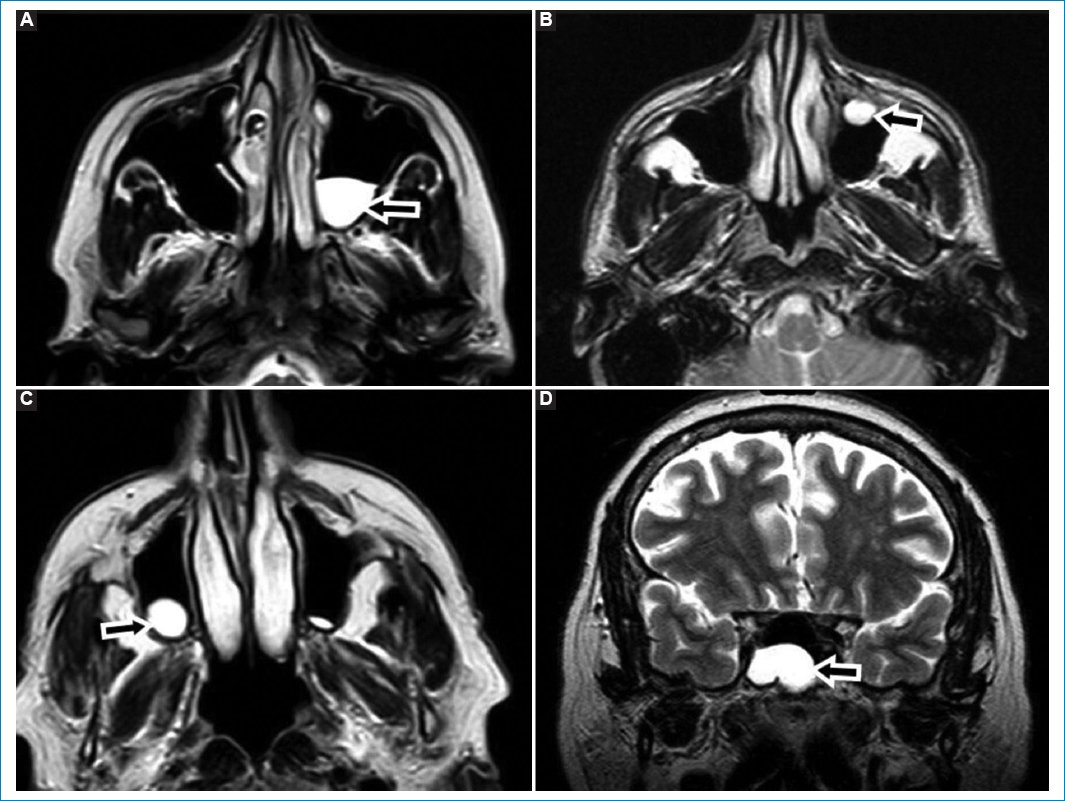

El quiste de Thornwaldt (QT) es una lesión benigna de la línea media de la nasofaringe, derivada de restos de la notocorda y el endodermo faríngeo21,22. Presenta una incidencia del 1,4-3,3%. Frecuentemente asintomáticos, pueden obstruir la vía aérea si crecen u ocasionar trastornos auditivos o dar síntomas si se infectan21,22. Suelen descubrirse en forma incidental mediante estudios por imágenes, realizados por otro motivo21.

La RM es el método de elección, apreciándose hiperintensos en T1 y T2, dado su rico contenido proteico, suelen no realzar con gadolinio (Fig. 5)21,22.

Figura 5. Quiste de Thornwaldt. Corte axial (A) y coronal (B), potenciados en T2. Las flechas señalan la presencia de una imagen de apariencia quística, hiperintensa en T2, en la pared posterior de la rinofaringe, compatible con QT.